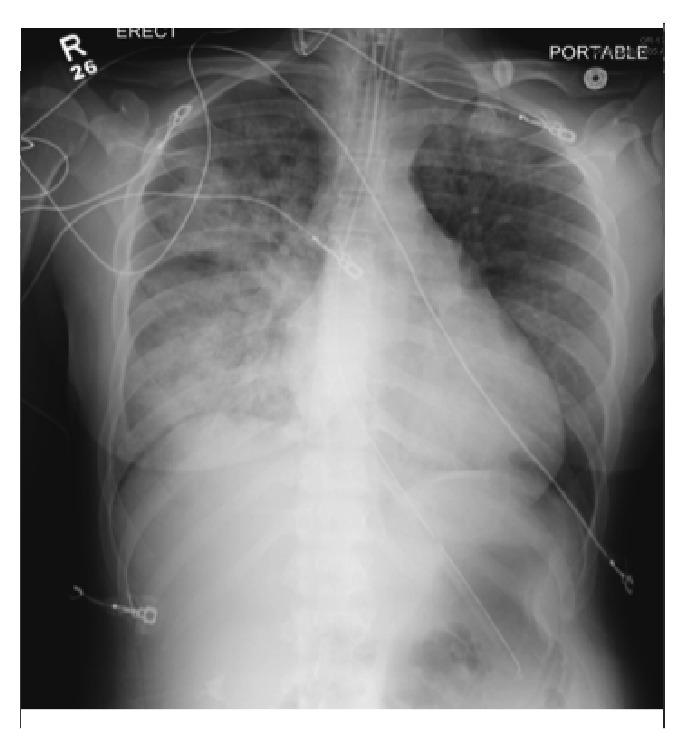

未确诊的格雷夫斯病患者因勒颈引发甲状腺风暴

Thyroid Storm Triggered by Strangulation in a Patient with Undiagnosed Graves' Disease.

Thyroid storm is the life-threatening end-organ manifestation of severe thyrotoxicosis. If left untreated, thyroid storm may cause acute heart failure, multiorgan dysfunction, and death. A high degree of suspicion is necessary to make the diagnosis and start antithyroid medications to decrease mortality. Thyroid storm is generally seen in patients with Graves' disease but should also be suspected in patients with fever, tachycardia, altered mental status, and risk factors including local trauma to the neck, such as strangulation. Based on our review, we report the first case of thyroid storm after strangulation as the presentation of previously undiagnosed Graves' disease.

摘要

甲状腺危象是严重甲状腺毒症危及生命的终末器官表现。若不治疗,甲状腺危象可能导致急性心力衰竭、多器官功能障碍及死亡。做出诊断并开始使用抗甲状腺药物以降低死亡率需要高度怀疑。甲状腺危象通常见于格雷夫斯病患者,但对于发热、心动过速、精神状态改变且有颈部局部创伤等危险因素(如勒颈)的患者也应怀疑。基于我们的综述,我们报告了首例以勒颈为表现形式的甲状腺危象,其为既往未诊断的格雷夫斯病。